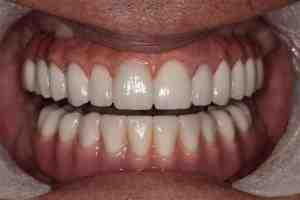

A cost-effective long-term solution In the long run, dental implants can be a cost-effective solution, and of course, they will look and feel amazing. On the same subject : Best Dental Implants. Regular maintenance is important and you should see your dentist for dental examinations and hygiene appointments.